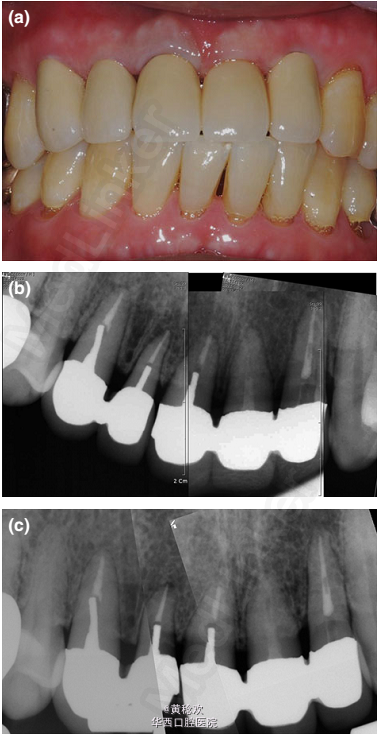

外伤冠折后的修复一例

患者60岁,男性,6周前上颌前牙区外伤冠折(颈缘),在当地牙科诊所已行牙髓切断术。